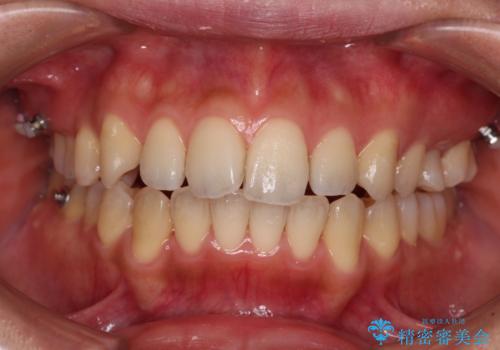

残存乳歯とオープンバイト インビザラインによる矯正治療

- 前歯のデコボコと咬み合わせを気にして来院された患者様です。

左上奥歯には乳歯が残存しており、後続永久歯は舌側に転位していました。

また、舌の突出癖の影響で上下前歯が接触していないオープンバイトとなっており、奥歯に負担のかかる咬み合わせとなっていました。

舌のトレーニングをしっかりと行ってくださり、前歯部のオープンバイトは大幅に改善されました。

もう少しでよりタイトに前歯が接触できそうでしたが、患者様がもう十分とのことで治療を終了しました。